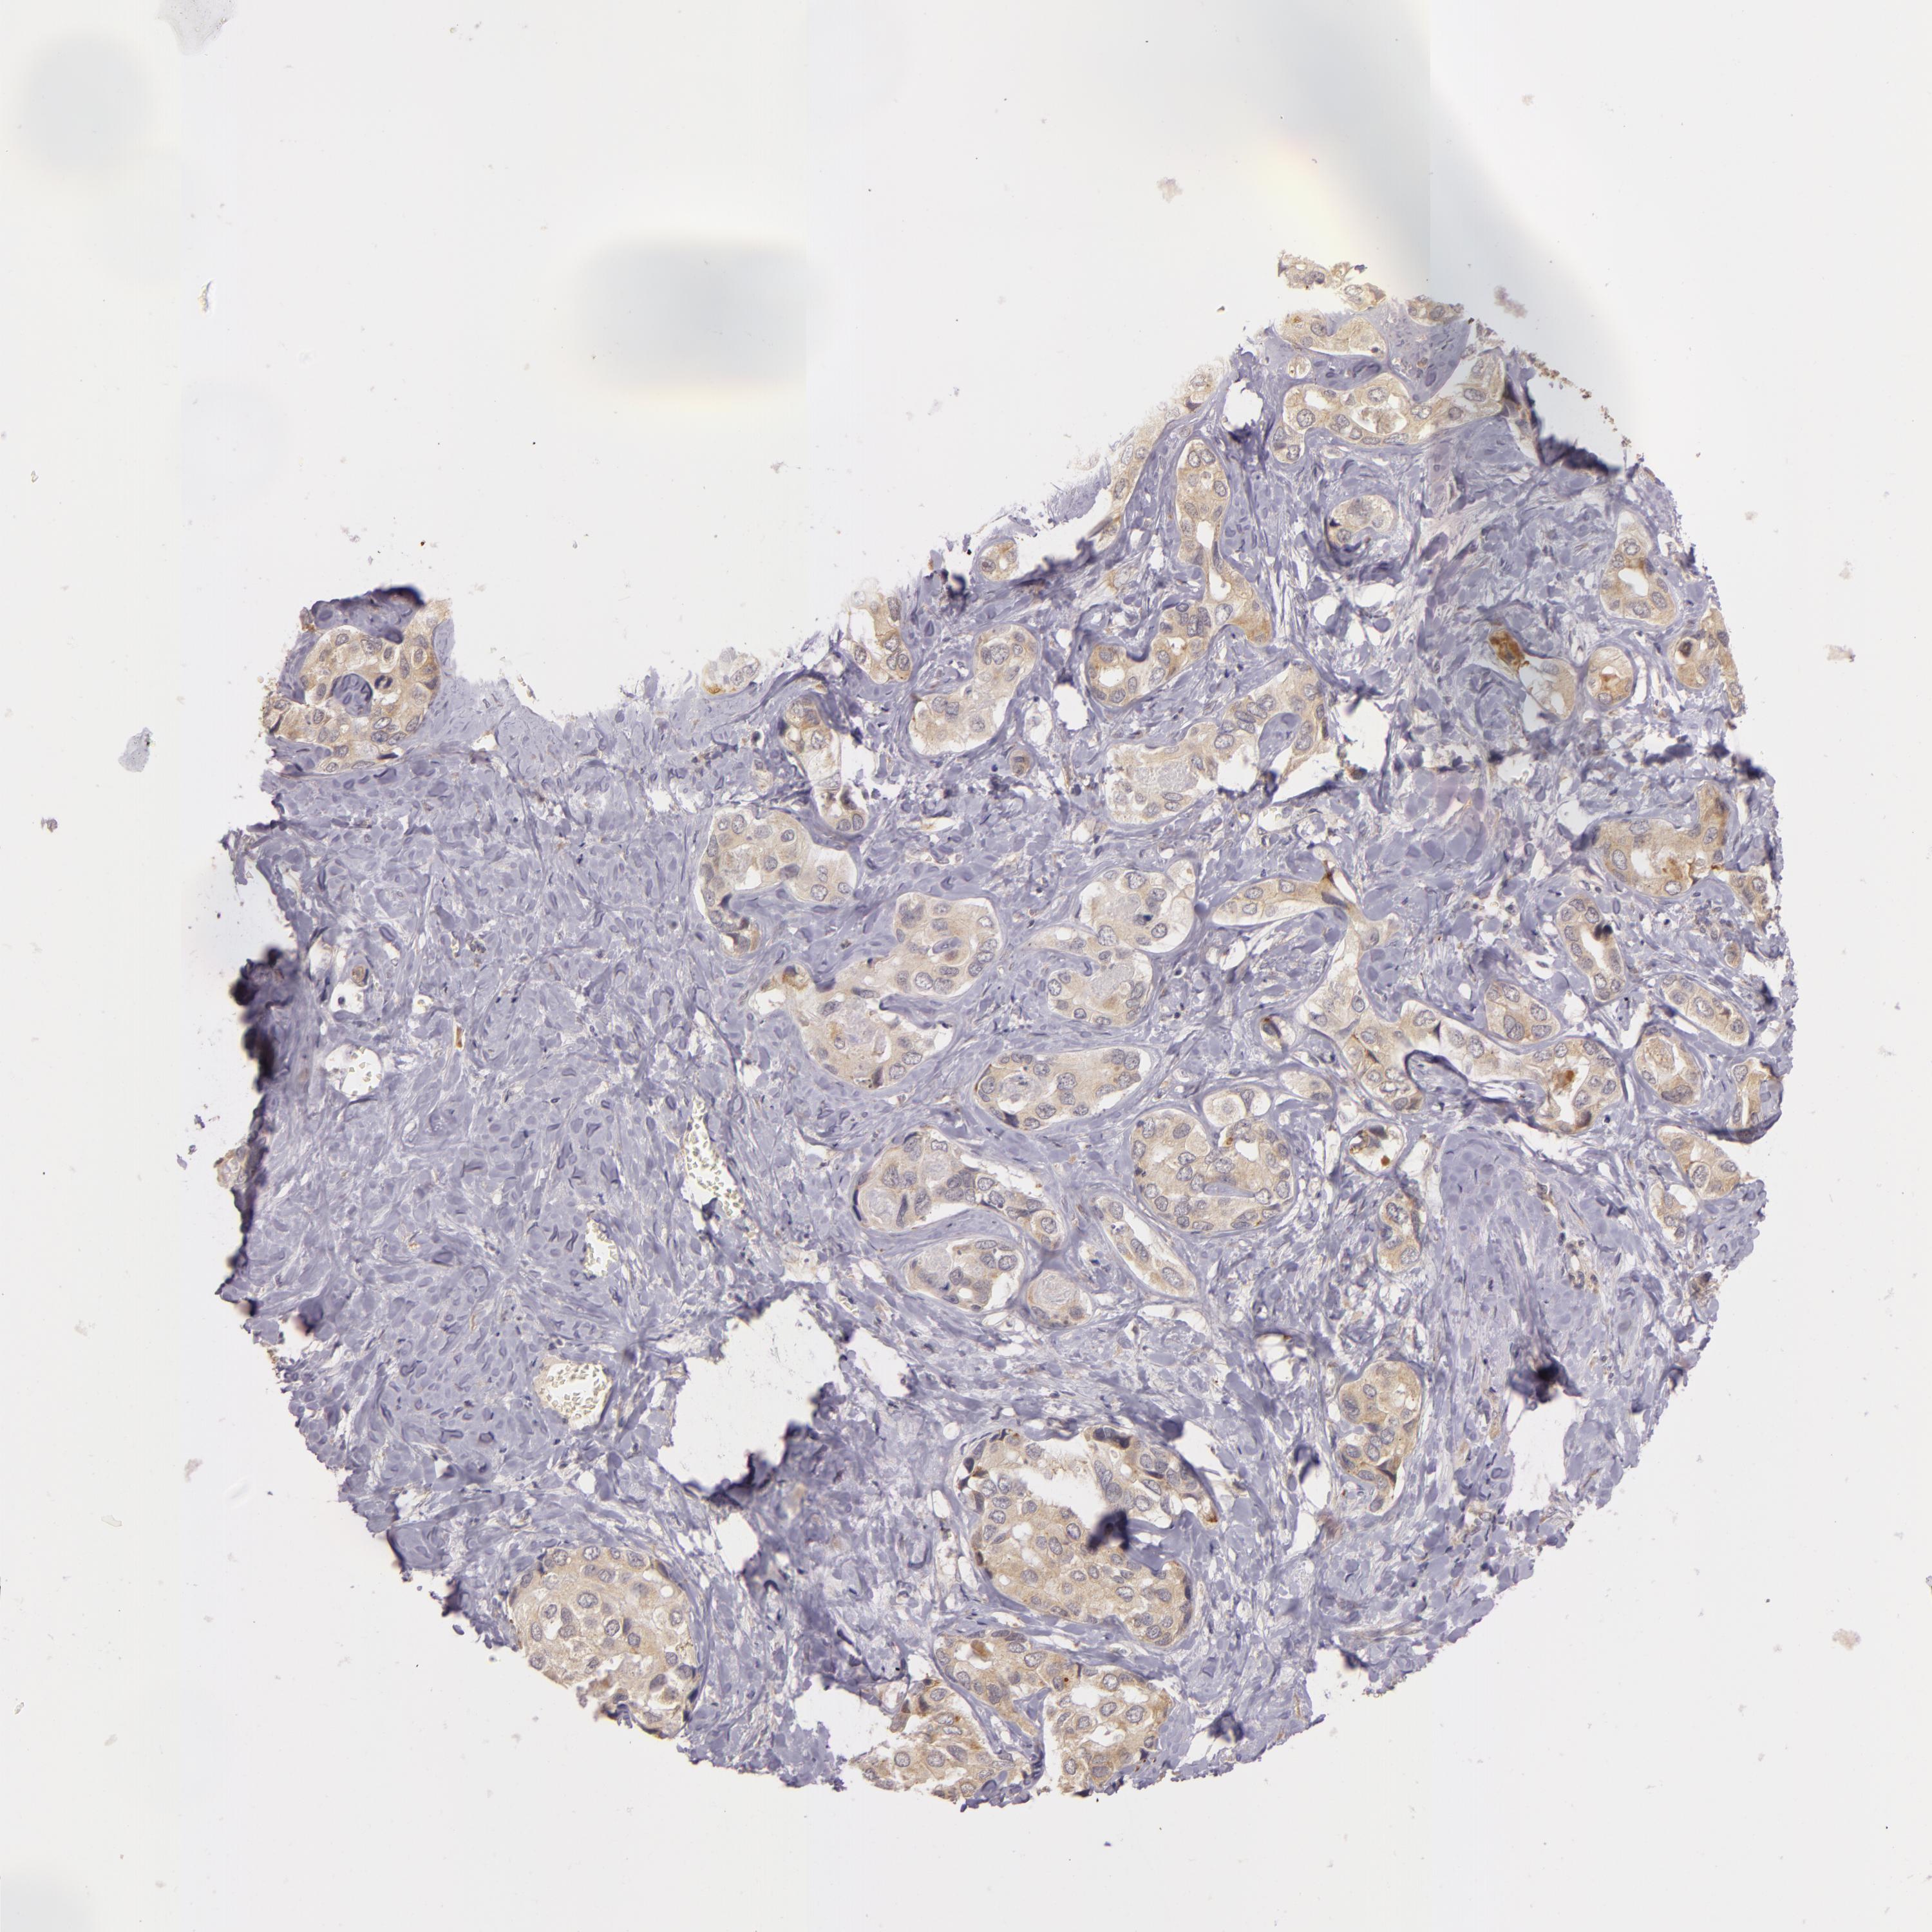

LIVER CANCER - Protein expressioni

A mouse-over function shows sample information and annotation data. Click on an image to view it in a full screen mode. Samples can be filtered based on level of antibody staining by selecting one or several of the following categories: high, medium, low and not detected. The assay and annotation is described here.

Note that samples used for immunohistochemistry by the Human Protein Atlas do not correspond to samples in the TCGA dataset.

Antibody stainingi

Antibody staining in the annotated cell types in the current human tissue is reported as not detected, low, medium, or high, based on conventional immunohistochemistry profiling in selected tissues. This score is based on the combination of the staining intensity and fraction of stained cells.

Each image is clickable and will lead to virtual microscopy that enables deeper exploration of all samples and also displays staining intensity scores, fraction scores and subcellular localization as well as patient and tissue information for each sample.

Antibody HPA000918

Staining

High

Medium

Low

Not detected

Intensity

Strong

Moderate

Weak

Negative

Quantity

>75%

75%-25%

<25%

None

Location

Nuclear

Cytoplasmic/membranous

Cytoplasmic/membranous,nuclear

Cholangiocarcinoma